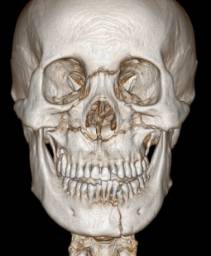

放射检查:一般包括X线头影测量片、曲面体层片和CBCT(锥束CT)。有时还包括其他放射检查,比如螺旋CT等。通过放射检查,医生可以看到骨骼及牙齿的形态、位置及发育状况,以及是否有牙体、根尖周、牙周疾病等,从而评估是否需要正畸治疗、进行何种治疗。

头影测量片(上)、曲面体层片(中)和锥束CT(下)